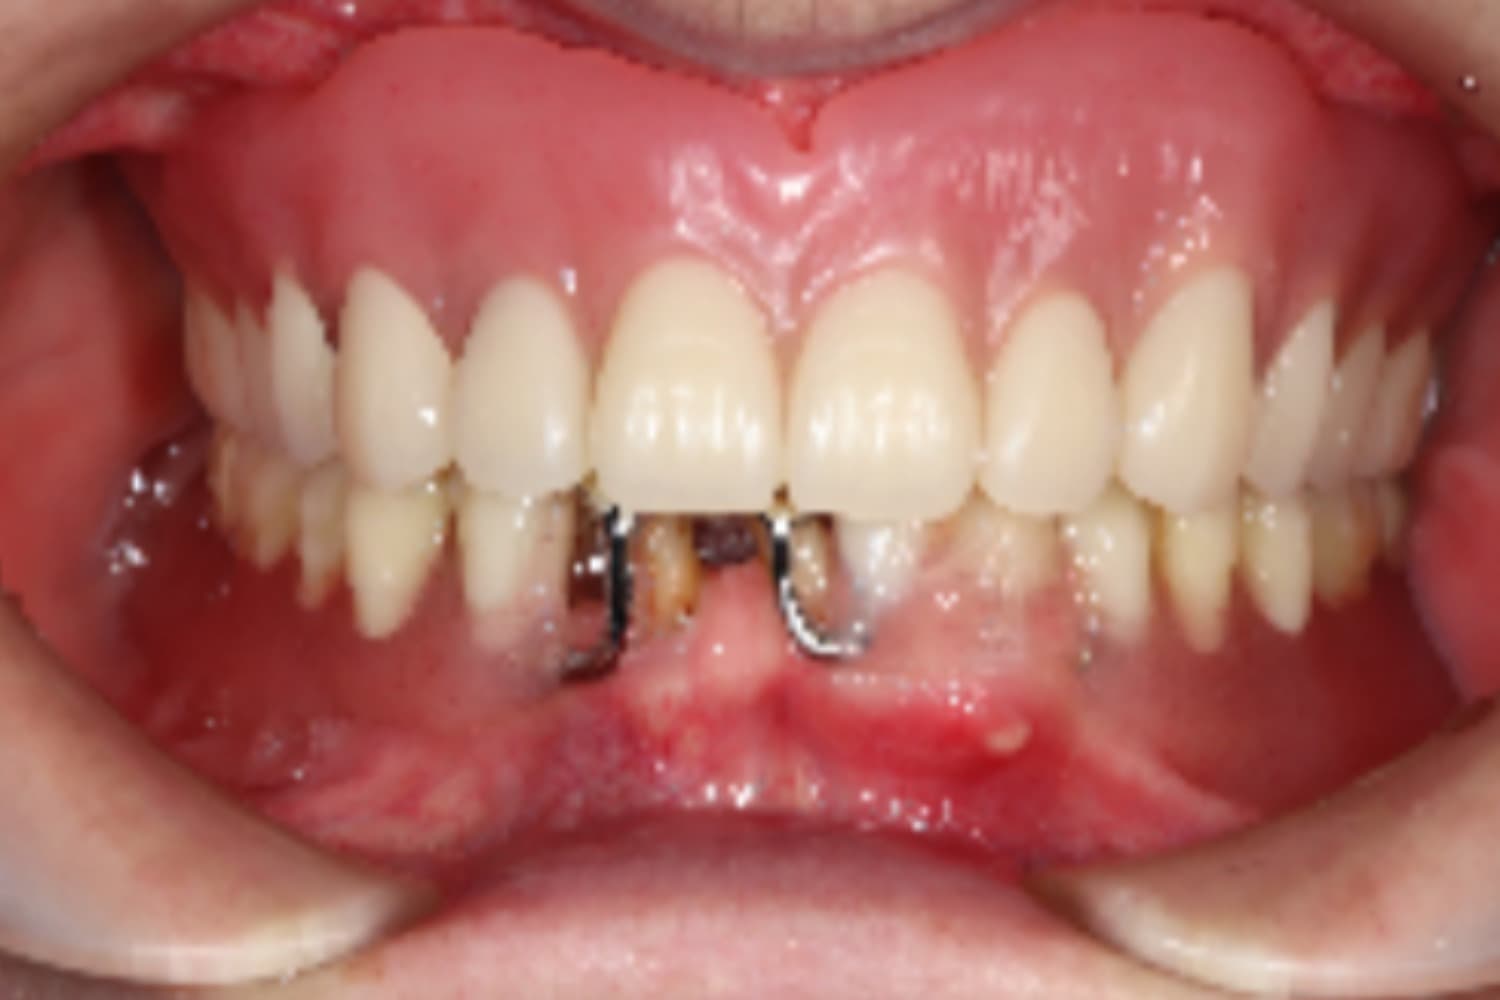

下顎すべてのインプラント治療

Before

After

下の前歯は抜歯と同時にインプラント4本を埋入し、その日に仮歯を装着してます(All-on-4)。

主訴

下の前歯がぐらぐらする

治療期間

6カ月

治療回数

12回

費用

3,080,000円

副作用・リスク

・インプラント埋入時の神経損傷リスクがあります。